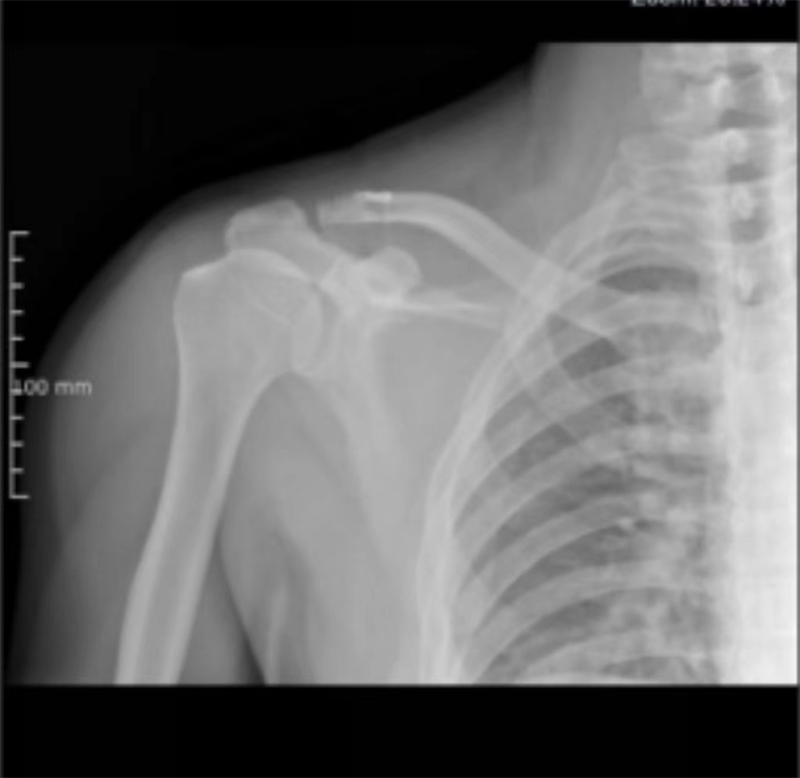

近期,寿光和信医院骨外科采取肩锁关节脱位切开复位袢钛板内固定术,一锚双袢固定,为肩锁关节脱位患者提供了一种全新的治疗选择。

传统一般都是使用锁骨钩钢板治疗肩锁关节脱位,术中将尖钩紧贴肩峰下缘插入肩锁关节后方的肩峰下,3~4枚螺钉将钢板固定于锁骨,可获得良好的疗效。但钢板内固定术后最常见的并发症是肩部疼痛、肩峰下黏连导致肩关节术后活动受限及钩尖所致的肩峰切割,还需要二次手术取出钢板等,给患者带来很多不便。

肩锁关节脱位是创伤骨科的一种常见疾病,而肩锁关节脱位切开复位袢钛板内固定术则为这些患者带来了曙光。术后功能良好,肩锁关节脱位Ⅲ度新鲜损伤生物重建有优势,美容缝合,不用二期取出内固定,简单、实用、美观、功能良好,比钩钢板固定有很大优势。通过及时的治疗和正确的康复措施,患者完全可以告别肩锁关节疼痛带来的困扰,重新拥有健康和快乐的生活。